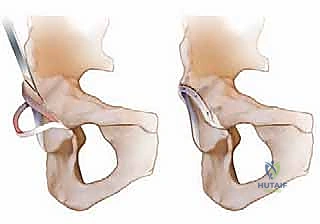

شكل 1أ • تصوير تخطيطي لانحشار الكام. في انحشار الكام، يتم دفع منطقة اتصال رأس وعنق الفخذ الأمامية الجانبية غير الكروية إلى الحُق، مما يخلق إصابة قص وإجهاد للغضروف الحقي على طول الحافة الأمامية العلوية.

شكل 1ب • تصوير تخطيطي لانحشار البنسر. في انحشار البنسر، يتم سحق الشفا الحقي بسبب التغطية الزائدة.

تنظير الورك (Hip Arthroscopy) ممتاز للحالات البسيطة، لكن في حالات التشوهات الكبيرة (الكام الضخم، أو ارتداد الحُق الشديد)، يوفر الخلع الجراحي المفتوح رؤية بانورامية بزاوية 360 درجة للمفصل بأكمله. الأهم من ذلك، يسمح هذا الإجراء للجراح بإعادة تشكيل العظام بدقة متناهية دون خطر الشد المفرط على الأعصاب (Traction injury) الذي قد يحدث في عمليات المنظار الطويلة.

التحدي المرعب تاريخياً في خلع مفصل الورك كان خطر الإصابة بـ النخر اللاوعائي (Avascular Necrosis - AVN)، وهو موت رأس الفخذ بسبب انقطاع الدم عنه. العبقرية في تقنية "غانز" التي يتقنها الدكتور هطيف تكمن في القدرة على خلع رأس الفخذ بالكامل من مكانه مع الحفاظ التام على الأوعية الدموية المغذية (الشريان المنعطف الفخذي الإنسي - Medial Circumflex Femoral Artery). يتم ذلك من خلال نهج جراحي دقيق للغاية يحمي العضلات والأوعية.